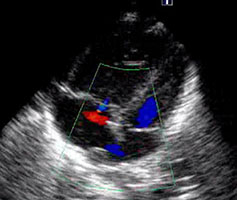

9、日齢15の新生児。呼吸障害と経皮的酸素飽和度の軽度低下を認め3日前から増悪した。心エコー図を示す。この症例で誤っているのはどれか。2つ選べ。

- 心拡大をきたす。

- 下大静脈が拡大する。

- 垂直静脈が下行している。

- 心房間交通は左右短絡である。

- 四腔断面像は新生児遷延性肺高血圧症と類似する。

正解:a, d